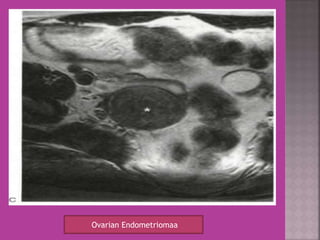

Ovarian Endometriomaa